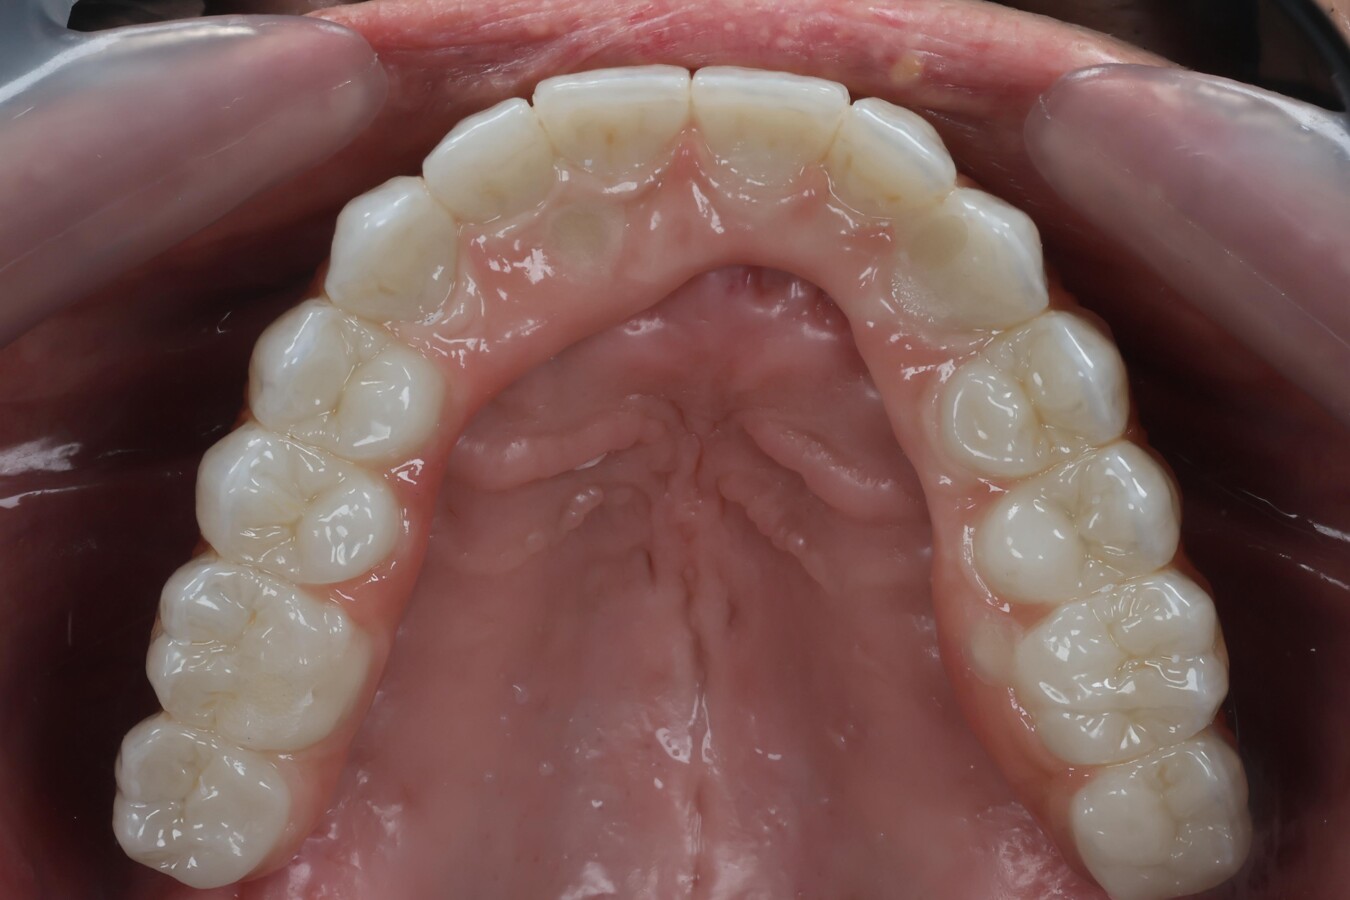

Figura 2. Scanbodies instalados sobre múltiples implantes dentales. Los puntos blancos son captados por el escáner y guían la reconstrucción digital, señalando la posición de los implantes. Foto: Marinelly Mendes

La fotogrametría funciona mediante un dispositivo que captura simultáneamente la posición exacta de los scanbodies colocados sobre los implantes.

El sistema toma múltiples imágenes calibradas y un software las interpreta para generar un modelo digital donde cada implante queda registrado con los siguientes parámetros:

• Posición exacta (X, Y, Z)

• Inclinación

• Distancia entre implantes

• Relación espacial entre todos los pilares.